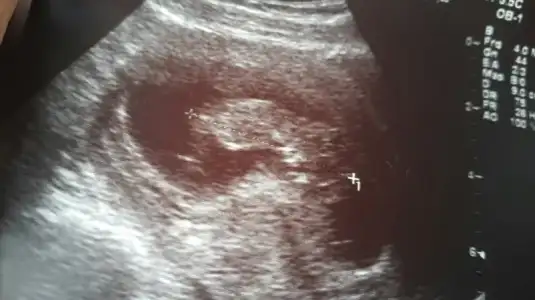

Kızlar üç günlük rapor yazdı düsuk tehditi var die. Yatış yapcakti istemedim. Bu da fotosu 11+0 . Aranızda cinsiyet tahmini yapabilecek var mı. Biliorum çok erken ama . Tahmin sonuçta söyleyin bişiler;) ;)

• 2015-11-17 12.53.54.webp

2015-11-17 12.53.54.webp

21 KB · Görüntüleme: 129